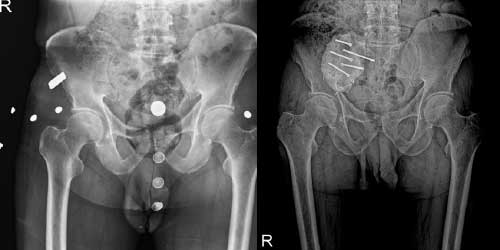

Omurga metastazı, kanserin ilk olarak iç organlarda gelişip daha sonra omurga kemiklerine yayılması sonucu oluşan bir durumdur. Çoğunlukla kan yoluyla sıçrayan bu tür metastaz, hastalarda sırt ve bel ağrısı gibi şikayetlerle kendini gösterir. Erken teşhis ve uygun tedavi yöntemleri, hastaların yaşam kalitesini artırmada kritik bir rol oynar.

Tedavide başarıyı artıran en önemli etkenlerden biri ameliyat öncesi iyi bir hazırlık ve cerrahi planlama yapmaktır. Her şeyden önce tanı doğru konmalı. Bunun için hasta iyi dinlenip, detaylı muayene edildikten sonra tetkikleri dikkatli incelenmelidir.